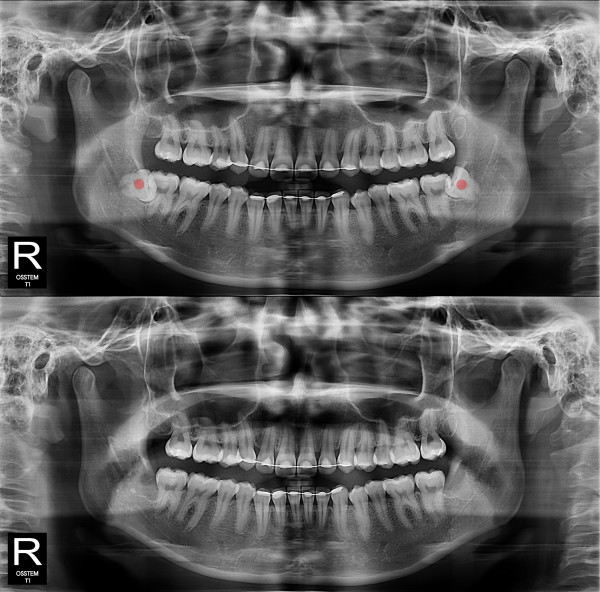

사랑니발치 완전 매복 사랑니

98c9148a81c37bd910ebd0e3dd27d654_1764730193_127.jpg